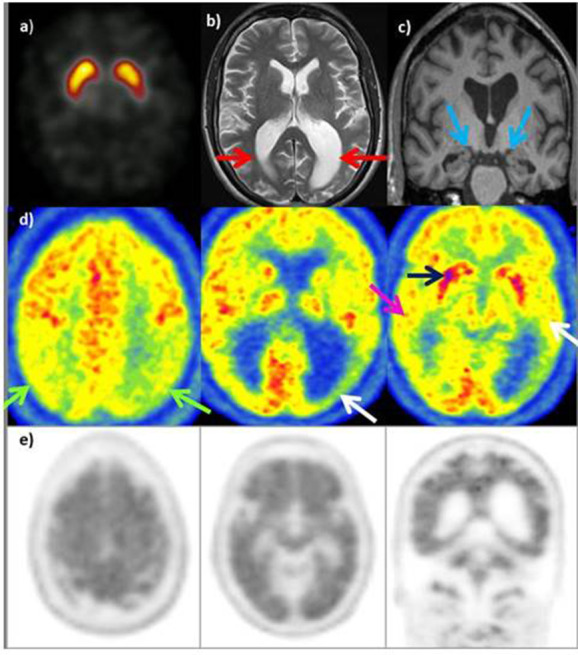

Atrofia Corticale Posteriore (PCA) – Variante visiva

La PCA rappresenta una variante “posteriore” dell’Alzheimer, caratterizzata da un esordio con disturbi della visione di alto livello.15

Dal punto di vista metabolico, si osserva un ipometabolismo marcato nelle regioni occipito-parietali e temporali posteriori.16 A differenza dell’AD tipico, il coinvolgimento della corteccia visiva primaria può essere presente, e il deficit parietale è spesso più grave ed esteso.

(B) PCA: ipometabolismo nelle aree occipitali e parietali e un relativo ipermetabolismo nel lobo frontale.